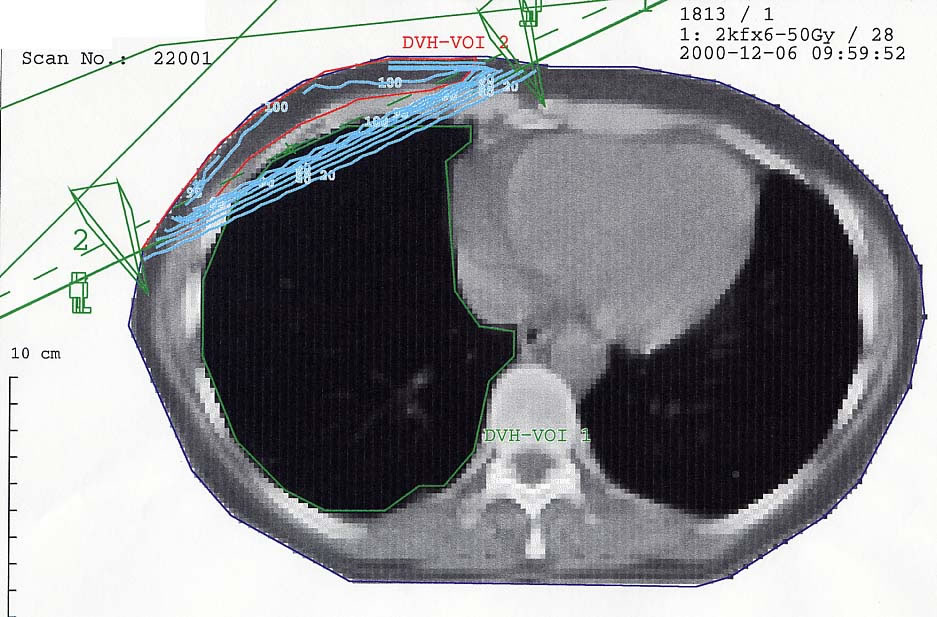

Mammakarzinom: Bestrahlungsplan